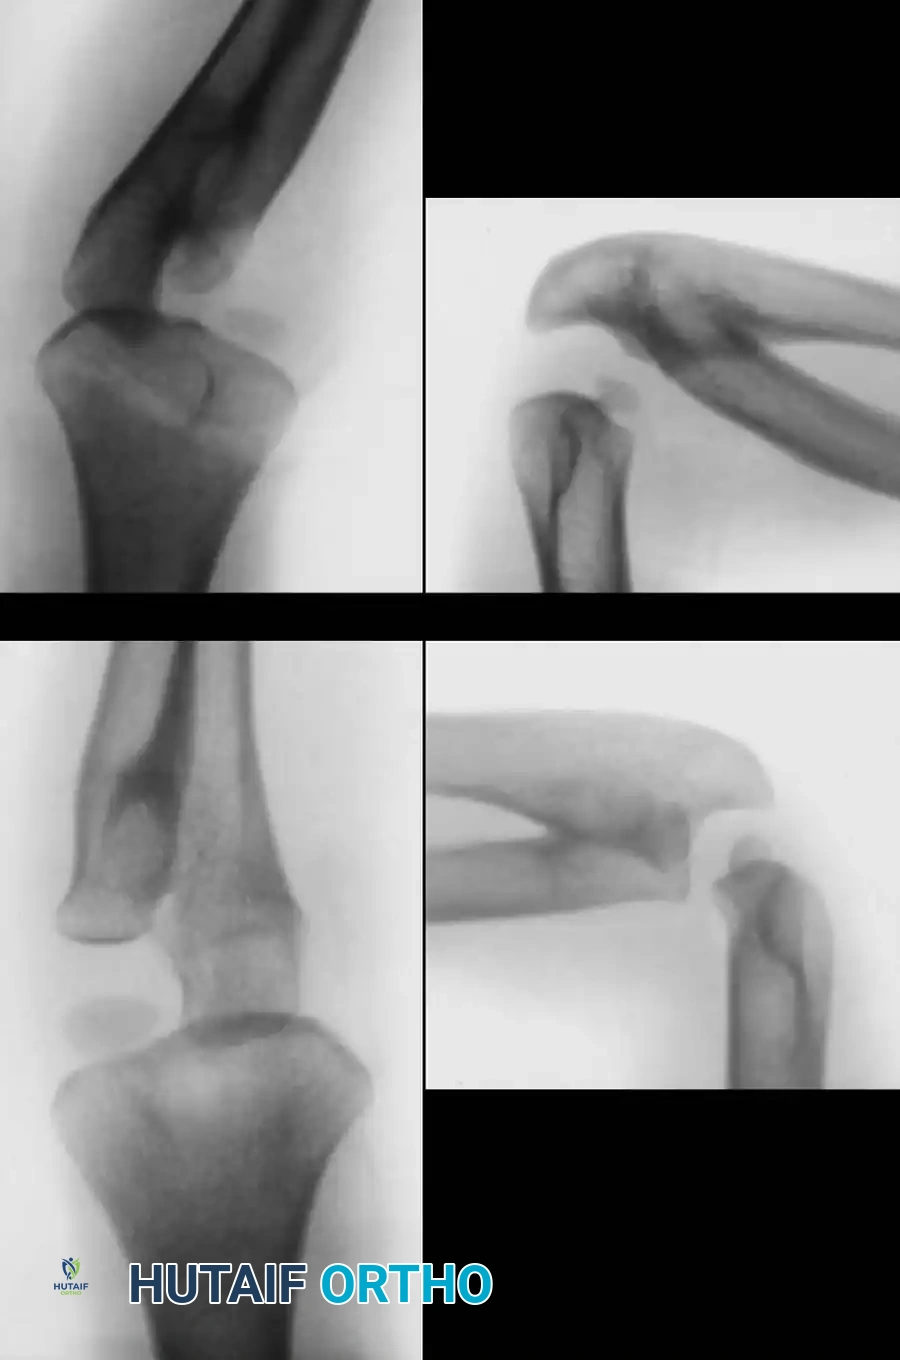

Wilkie Classification of Congenital Radioulnar Synostosis. A and B: Type I, demonstrating proximal fusion for several centimeters with an enlarged, bowed radius. C and D: Type II, demonstrating posterior and lateral dislocation of the proximal radius with a more focal fusion mass.

- Type I: The medullary canals of the proximal radius and ulna are seamlessly joined. The proximal radius is malformed and fused to the ulna over a distance of several centimeters. The radius is typically longer and more robust than the ulna, and its diaphysis arches anteriorly more than normal.

- Type II: The radius is morphologically fairly normal, but its proximal end is dislocated (either anteriorly or posteriorly) and fused to the proximal ulnar shaft. The fusion mass is neither as extensive nor as intimately medullary as in Type I. Wilkie noted that Type II is more frequently unilateral and may be associated with other congenital anomalies, such as syndactyly, supernumerary digits, or thumb aplasia.